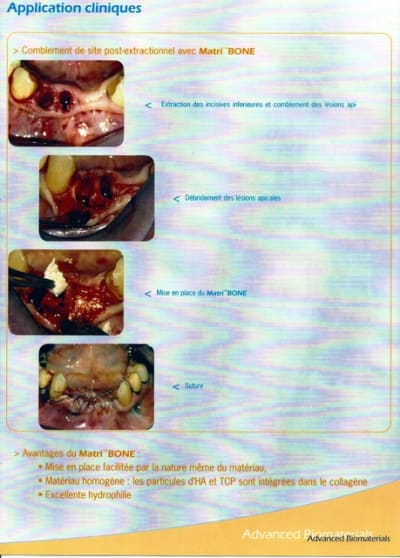

bon, retrouvé la plaquette...c'est le "matri bone" qui est une sorte d'éponge hémostatique de collagène avec particules d'hydroxyapatite et de TCP...

avantages:

prix...

se manipule comme une éponge...

après reste à voir si çà marche bien...